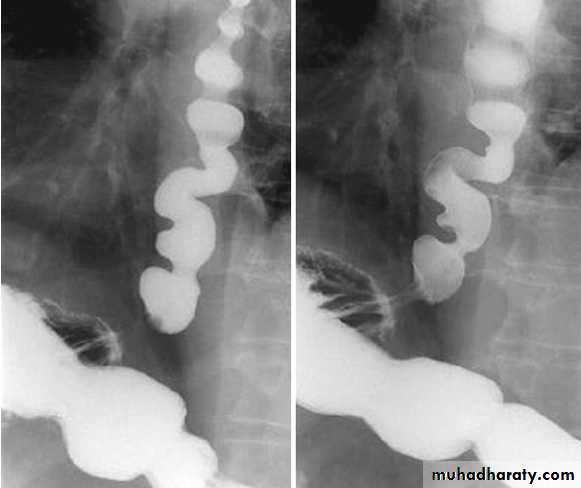

• Stricture: benign and malignant / causes / specific location

• Filling defect: types and causes• Diverticulum: types and causes

• Ulcer: benign vs. malignant/ size

• Mucosal alteration

• Contour changes: physiological vs. pathological

• Dilatation: obstructive vs. non-obstructive